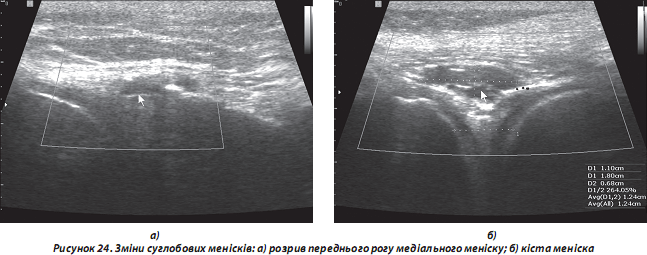

д) зміни суглобового хряща, менісків (зокрема, часткові та повні розриви), судин та інших м’якотканинних структур (рис. 24);